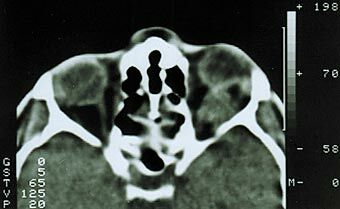

Первый тип опухоли характеризуется субдуральным ростом менингиомы вдоль ствола зрительного нерва. Частота подобного роста на нашем материале составила 41% случаев. Клинически обращает на себя внимание раннее нарушение периферического зрения с постепенным снижением центрального. В начале заболевания на фоне стойкого сужения поля зрения (концентричного или асимметричного) ухудшение центрального зрения носит интермиттирующий характер. Стойкая утрата зрительных функций наступает поздно, когда развивается атрофия диска зрительного нерва. Экзофтальм, чаще всего осевой, возникает спустя 2–3 года после появления зрительных расстройств, бывает небольшим и никогда не превышает 6–7 мм (рис. 1). Функции экстраокулярных мышц сохранены в полном объеме. Диагностировать менингиому в подобных случаях трудно даже с помощью компьютерной томографии или МРТ-исследования, так как диаметр зрительного нерва может быть увеличен незначительно (рис. 2).

Рис. 2. Компьютерная томограмма той же больной. Видна тень увеличенного зрительного нерва.